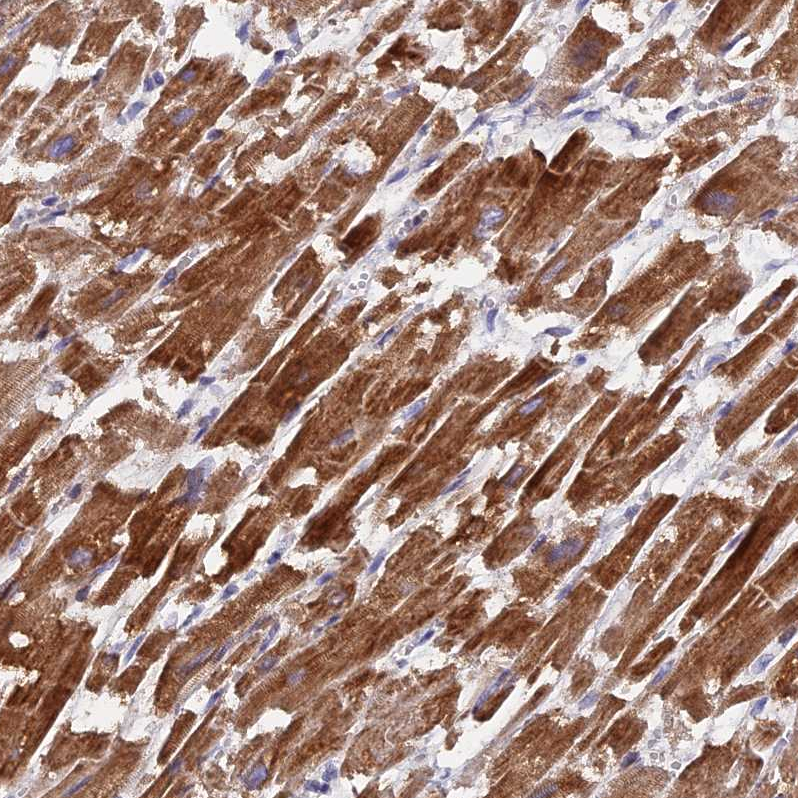

Immunohistochemical staining of human skeletal muscle shows strong cytoplasmic positivity in myocytes.